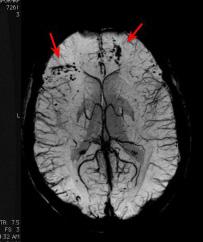

The brain in this scan from an MRI has a brain bleed in the frontal cortex, which can happen during a concussion, said Carol DeMatteo, professor of rehabilitation science at McMaster University. Media used with permission by Carol Dematteo